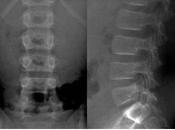

Caso clínico enarm

Masculino de 46 años de edad, sufre caída de una altura promedio de 5 metros, al parecer cae sobre la cabeza. A su llegada al servicio de urgencias se recibe... Leer el resto